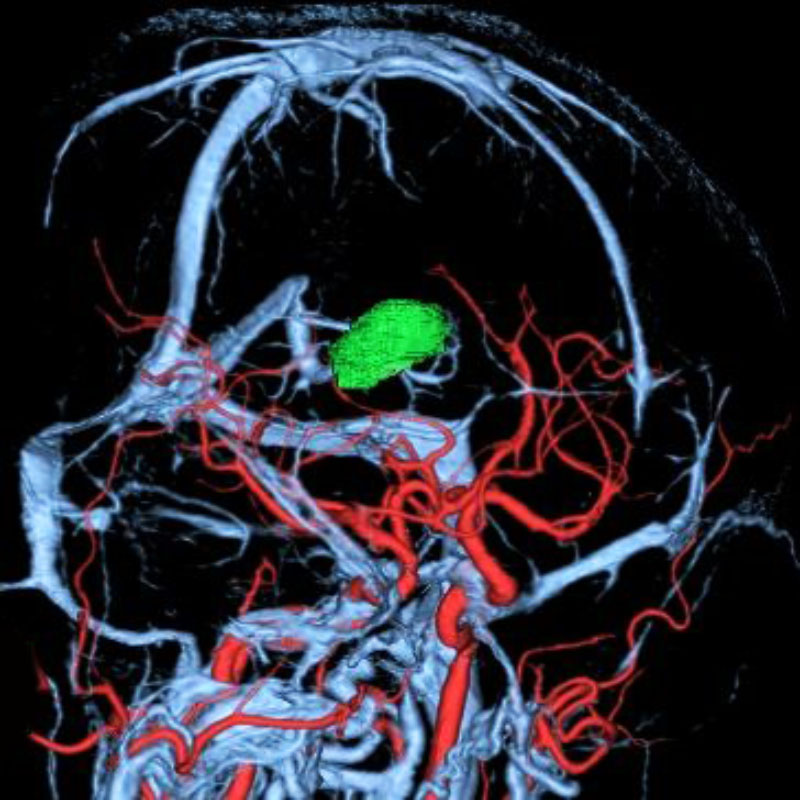

脳動静脈奇形

血管塞栓術

松田/濵田/元永